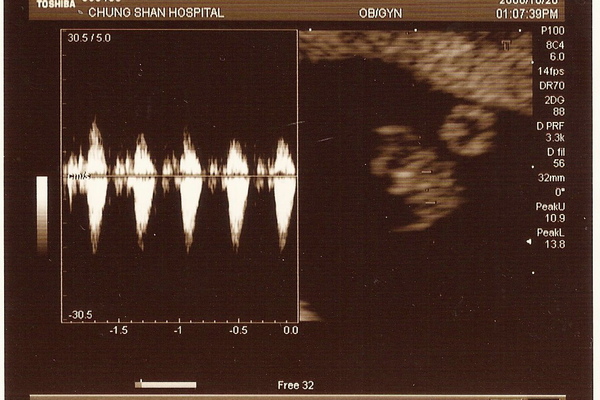

再來醫生又繼續移動機器。"砰砰砰砰~~" 聽到一陣好大聲又快速的心跳聲。醫生說小牛一切正常,心臟很強而有力的跳動著喔!

這就是小牛的心跳啦! 我們是健康活潑的牛寶寶喔!